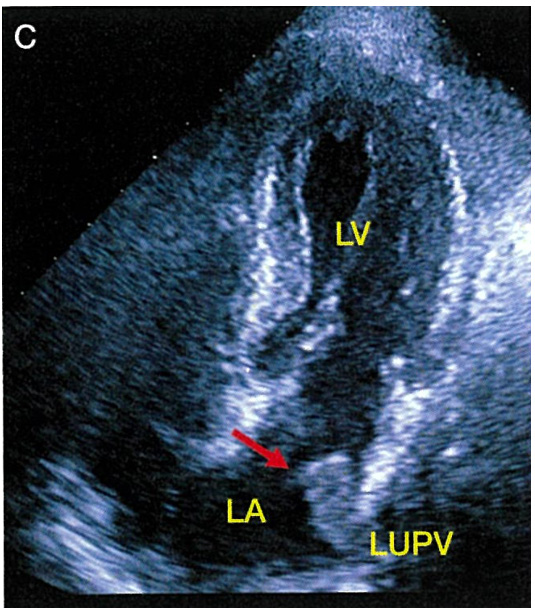

| 276 | 図5 図説 | A:右房内にIVC から伸びる異常エコーがみられる. B:症例Aの…された.子宮肉腫であり,… C:肺静脈から左房へ伸びる腫瘤が観察される.肺がんからの… |

A:右房内にIVC から伸びる異常エコーがみられる(矢印). B:症例Aの…された(矢印).子宮肉腫であり,… C:肺静脈から左房へ伸びる腫瘤が観察される(矢印).肺がんからの… |

| 276 | 図5 C | ![]() |

![]() |